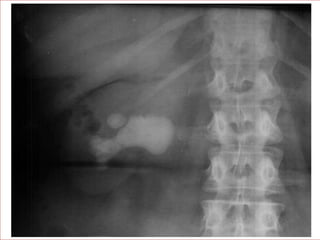

ABDOMEN

• Decúbito supino.

• Tamaño, forma, situación y

coexistencia de anomalías en

su contorno.

• Superposición de gas y

heces.

• Otras patologías

extrarrenales.

RADIOGRAFÍA SIMPLE DE ABDOMEN •Decúbito supino. • Tamaño, forma, situación y coexistencia de anomalías en su contorno. • Superposición de gas y heces. • Otras patologías extrarrenales.